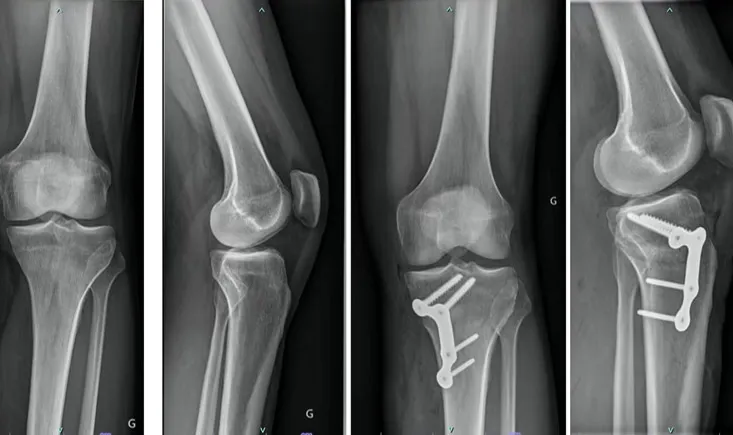

A 68-year-old woman has been suffering from mechanical bilateral knee pain for the past 6 years. The x-rays re…